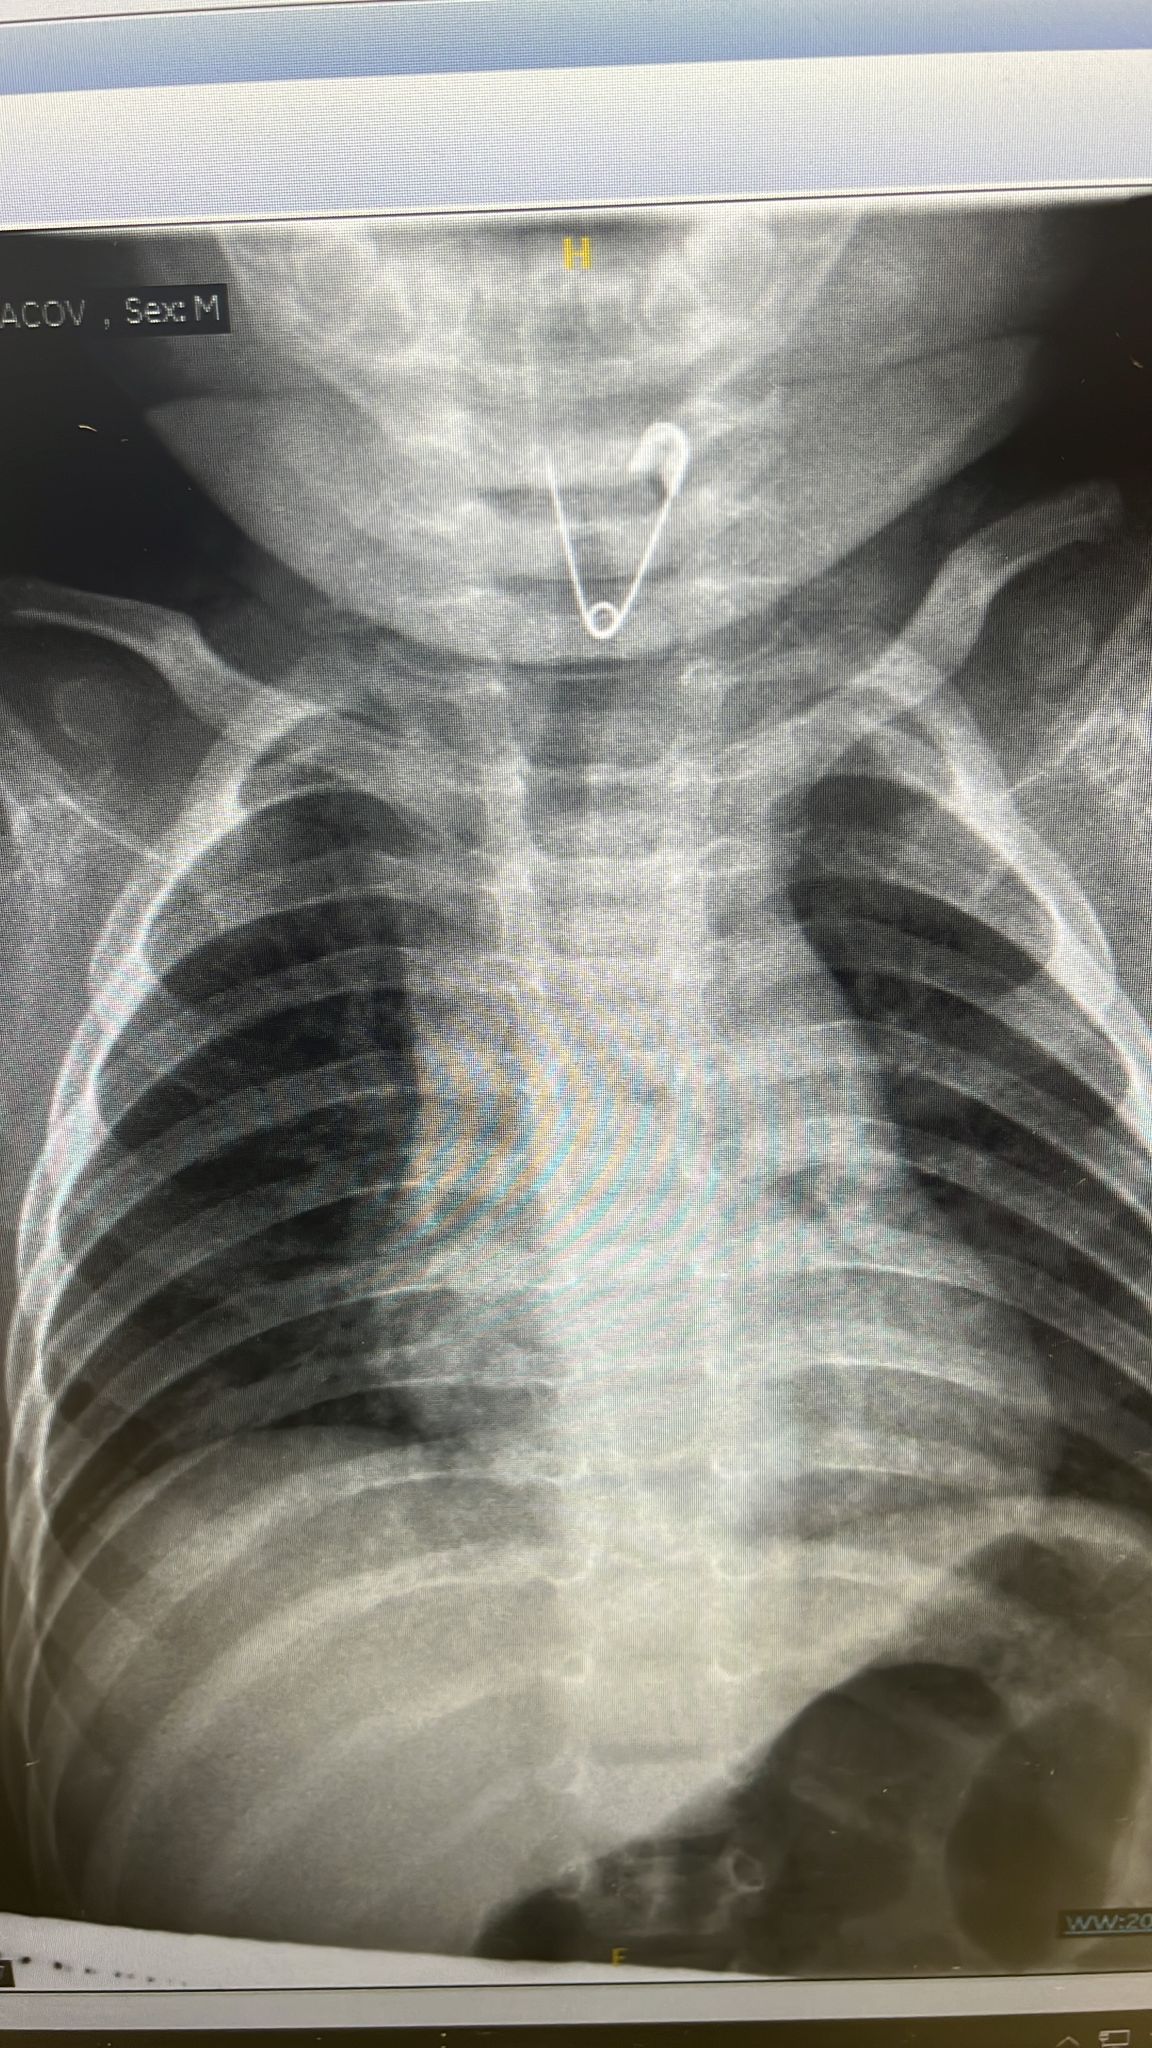

עם קבלתם במלר"ד ילדים הם טופלו ע"י ד"ר הגר גור סופרמן מנהלת המלר"ד. למרות מצבו המצוין בבדיקה הוא נשלח מיד לצילום רנטגן בו נצפתה סיכת בטחון פתוחה בכניסה לוושט

ד"ר הגר גור מנהלת מלר"ד ילדים: "בשעות הצהריים הובא למיון תינוק בן 8 חודשים אשר האב חשד שהכניס משהו לפיו כיוון שראה תנועות אי נוחות סביב הפה. במישוש בבית חשו בגוף זר ואף נצפה דימום קל. הובא אלינו במצב מצוין אולם לאור הסיפור המחשיד בוצע צילום, אשר להפתעת כולם הדגים סיכת ביטחון פתוחה ממוקמת בוושט העליון. מדובר במצב מסוכן בו עלול להיווצר חור על ידי הסיכה בוושט, לגרום לפציעה ודליפת חומצה לחזה ואף סכנת חיים.

למיון הוזעקו צוות אאג -דר ירדן מתמחה ודר שוורץ מומחה אאג ילדים אשר הבהילו את התינוק לחדר ניתוח. בחדר ניתוח תחת הרדמה מלאה שבוצעה עי דר מיכה שמיר הוצאה הסיכה בבטחה . האירוע לשמחתנו הסתיים היטב אולם מדגיש שוב את החשיבות ביצירת סביבה בטוחה והשגחה קפדנית על פעוטות בכלל ובתקופת החופשים בפרט